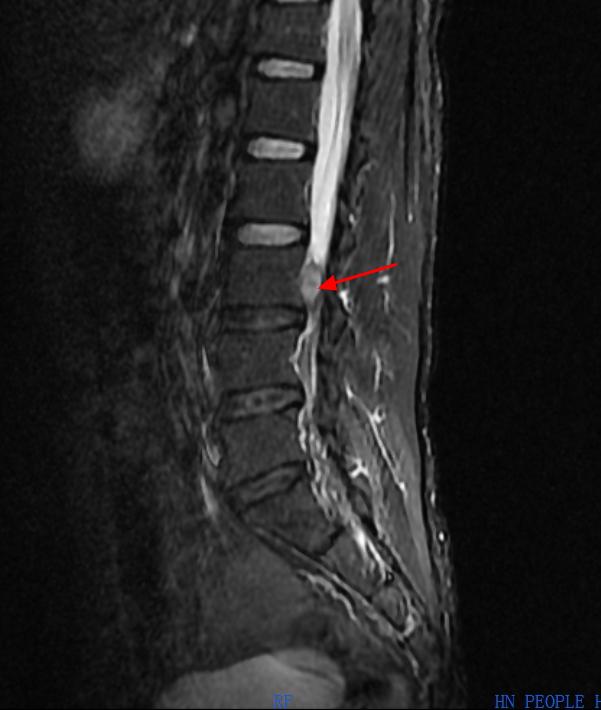

L3椎体对应椎管“占位”

接诊后,曹启旺主任仔细询问了彭先生的病史,以及进一步完善相关检查,腰椎增强核磁提示“腰3椎体左后方神经根走行区占位性病变,考虑神经源性肿瘤可能”,检查结果让彭先生一家慌了神,曹启旺主任却做了进一步考虑,凭借多年的行医经验,以及结合患者病史和症状,他综合判断彭先生椎管内占位神经源性肿瘤的可能性较小,更像是椎间盘脱出的组织,在与彭先生一家充分沟通后,决定为其实施脊柱内镜下椎管探查术。